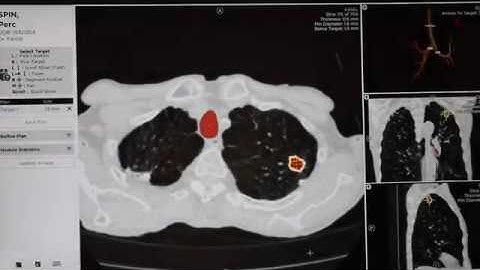

Automatic Pulmonary Nodule Detection in CT Scans Using Convolutional Neural Networks Based on Maximu